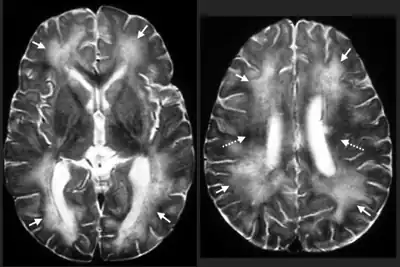

- Eye and brain tissue damage due to the random migration of the larvae.

- Severe neurological signs including imbalance, circling and abnormal behavior, caused by extensive tissue damage due to larval migration through the brain, eventually seizures and coma.

After an animal swallows the eggs, the microscopic larvae hatch in the intestine and invade the intestinal wall. If they are in their definitive host they develop for several weeks, then enter the intestinal lumen, mature, mate, and produce eggs, which are carried out in the fecal stream. If the larvae are in a paratenic host, they break into the bloodstream and enter various organs, particularly the central nervous system. A great deal of damage occurs wherever the larva try to make a home. In response to the attack, the body attempts to destroy it by walling it off or killing it. The larva moves rapidly to escape, seeking out the liver, eyes, spinal cord or brain. Occasionally they can be found in the heart, lungs, and other organs. Eventually the larva dies and is reabsorbed by the body. In very small species such as mice, it might take only one or two larvae in the brain to be fatal. If the larva does not cause significant damage in vital organs, then the victim will show no signs of disease. On the other hand, if it causes behavioral changes by destroying parts of the brain, the host becomes easier prey, bringing the larva into the intestine of a new host.